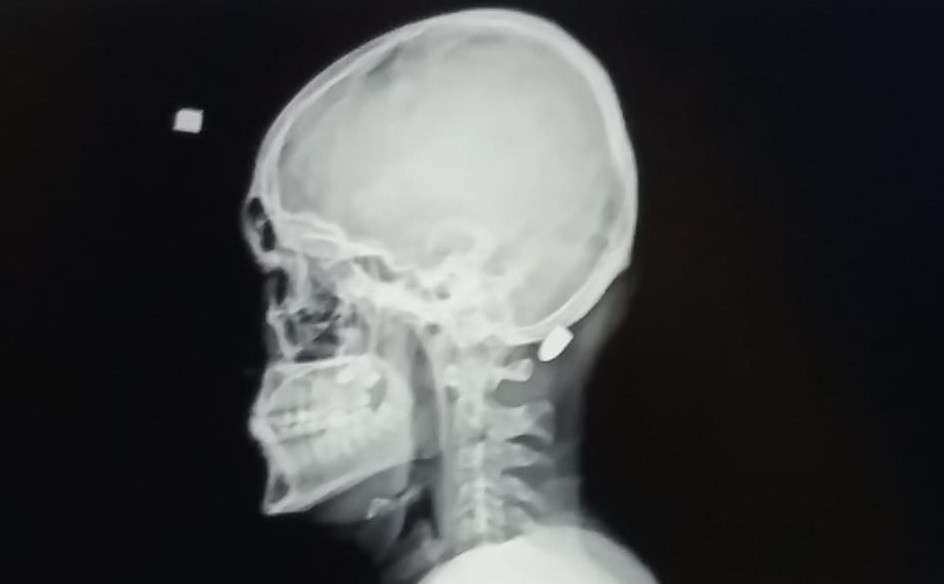

Trabzon’un Vakfıkebir ilçesindeki Karadağ Yaylası’nda bir evin dış cephe kaplamasını yapan 18 yaşındaki Ali Kuleyin’in başına nerden atıldığı belli olmayan kurşun isabet etmiş, ilk önce kurşun olduğunu anlamayan genç, elini başına götürdüğünde kan geldiğini anlayınca hastaneye kaldırılmıştı. İsabet eden yorgun mermi başarılı bir operasyonla saplandığı yerden çıkartılmıştı.